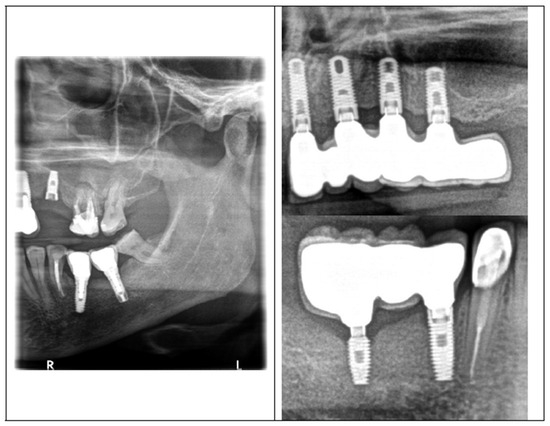

| 2 | anterior + lateral | bridge 6 pts. 21–26 | ZIMMER 3.7 mm × 13 mm ZIMMER 4.1 mm × 11.5 mm ZIMMER 4.1 mm × 10 mm ZIMMER 4.1 mm × 10 mm | The four screws tested attached a six-point bridge to implants in sections 21–26 (front and lateral sections of the maxilla, left side). Implant in the incisor area with a diameter of 3.7 mm and a length of 13 mm, implant in the canine area with a diameter of 4.1 mm and a length of 11.5 mm, in the area of the first premolar with a diameter of 4.1 mm and a length of 10 mm, and last implant in the area of the molar tooth with a diameter 4 and 10 mm long. Implant placement in 2016. The prosthetic work was installed in 2020, the screws lasted for three years. The patient did not come for regular check-ups and started treatment in another office, which resulted in overloading the bridge on implants 21–26 and breaking two of the four implant-fixing screws in the premolar and molar area. |